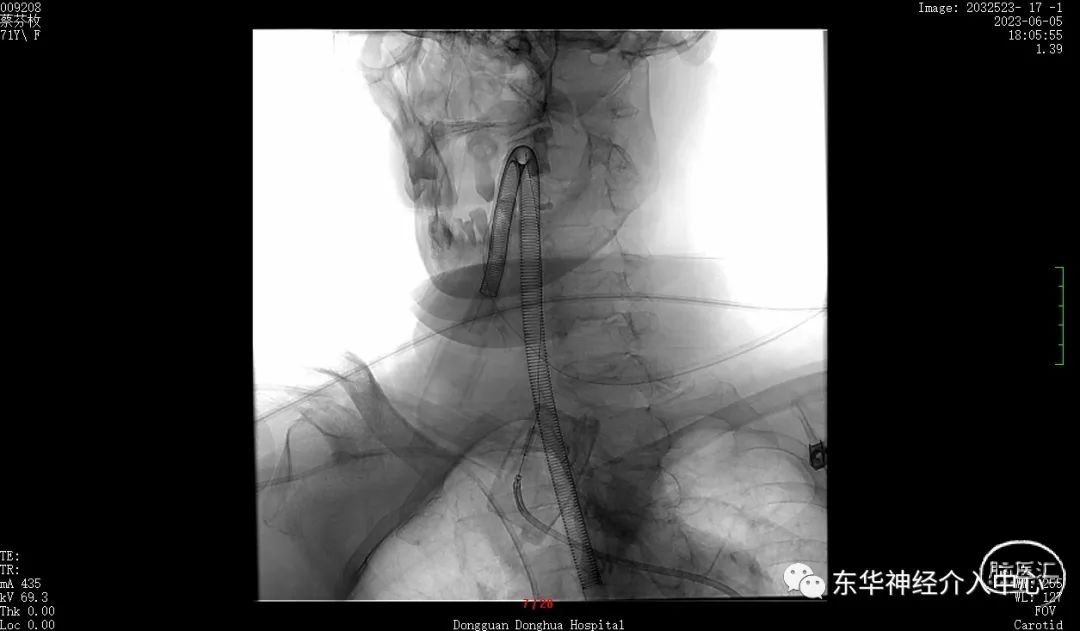

同侧椎动脉的开口狭窄,置入中间导管后血流不通畅。不得不进行开口的扩张。这倒是简单。扩张后顺利将中间导管置入合适位置。开始进行真正的动脉瘤栓塞术。

但是换用了三种微导丝都是难以将微导丝进入到PICA 的远端。考虑可能是动脉瘤稍远的PICA 内有斑块阻挡。微导丝不能到达远端,支架导管就不能进入其内,采取支架辅助栓塞动脉瘤已经不现实了。但是手术不可能放弃呀。曾经也拜读过有同道的文章采取微导丝来辅助栓塞动脉瘤、只能尝试一下了,但是风险更大、难度更高。不过令人欣慰的是经过反复的调整,第一个成篮圈非常满意。